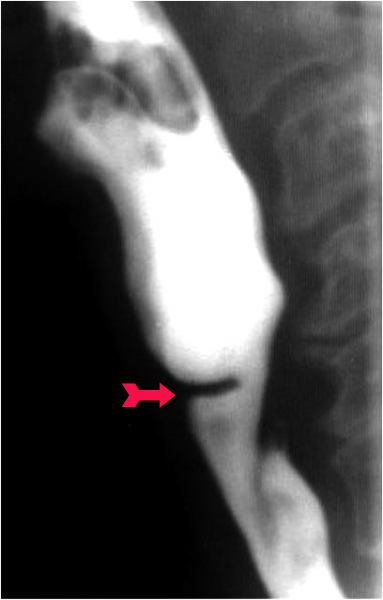

תסמונת זו, שתיארו Vinson ו-Plummer ב-1919, היא שכיחה בגיל הביניים ובנשים. התסמונת מאופיינת באנמיה כרונית ובמחיצה בוושט. האטיולוגיה המקובלת היא חוסר ברזל בדיאטה. לא לכל החולים יש אנמיה, ובמקצתם אין מחיצה של ממש. באחרים המחיצה היא מולדת. המקום השכיח יותר למציאת מחיצה מולדת הוא דווקא החלק התחתון של הוושט.

- הפרעה בבליעה (דיספגיה): נובעת מקיום מחיצה (Web) פיברוטית, החוסמת חלקית את נהור הוושט מילימטרים אחדים מתחילתו. 10% מהחולים יפתחו שאתות בלוע הפומי (אורופרינקס) ובוושט.